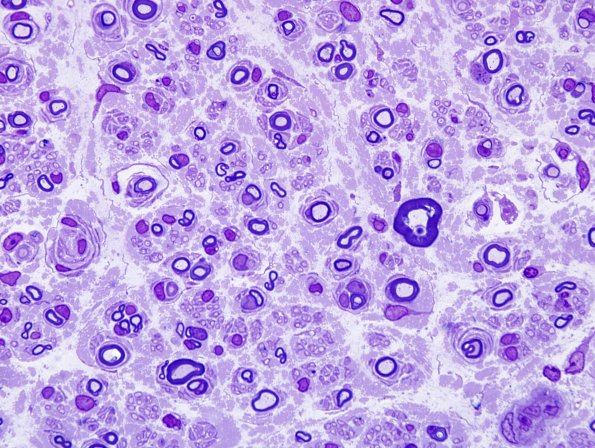

Washington University Experience | PERIPHERAL NEUROPATHY | 7B CIDP | 10A2 CIDP (Case 10) Plastic 2.jpg

These images show numerous axons with early onion bulb formation (arrows) and all stages of demyelination. (Plastic sections)